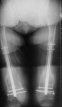

B. Fixation loosening: distal cutting of the nail, non-unions do happen (cases attached).

Locking Plating has more distal screws than any nail, fixed angles and provides much better fixation, especially in osteoporotic bone.